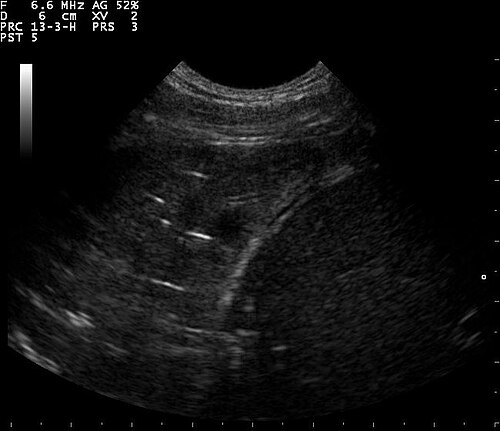

Lung Ultrasound — B-Lines (Pulmonary Fibrosis)

B-lines visible on lung ultrasound indicating interstitial disease in a patient with pulmonary fibrosis

ULTRASOUND Downloaded 2026-03-15

Ultrasound

B Mode

Wikimedia Commons: B lines on a lung ultrasound of a patient with fibrosis.jpg